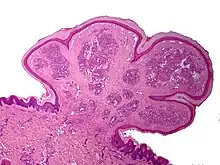

A pyogenic granuloma or lobular capillary hemangioma[3] is a vascular tumor that occurs on both mucosa and skin, and appears as an overgrowth of tissue due to irritation, physical trauma, or hormonal factors.[4][5] It is often found to involve the gums, skin, or nasal septum, and has also been found far from the head, such as in the thigh.[6]

The appearance of pyogenic granuloma is usually a color ranging from red/pink to purple, grows rapidly, and can be smooth or mushroom-shaped. Younger lesions are more likely to be red because of their high number of blood vessels. Older lesions begin to change into a pink color. Size commonly ranges from a few millimeters to centimeters, though smaller or larger lesions may occur. A pyogenic granuloma can be painful, especially if located in an area of the body where it is constantly disturbed. Pyogenic granulomas can grow rapidly and often bleed profusely with little or no trauma. They may exude an oil-like substance, causing the surface to be damp. This is especially true if the granuloma is located on the scalp.

One study has suggested a correlation between pyogenic granulomas and Bartonella seropositivity.[8] However, this association has been questioned by others.[9] The microscopic appearance of a pyogenic granuloma consists of highly vascular granulation tissue. Inflammation is present. The lesion may have a fibrous character if it is older, and the surface may have ulcerations. Pyogenic granulomas rarely occur in the conjunctiva, cornea, or connective tissue of the eye following minor local trauma. Grossly, these mass lesions resemble those occurring at more common sites. The relationship of these lesions to lobular capillary hemangiomas of skin and oropharyngeal mucosa commonly referred to as pyogenic granuloma is uncertain.